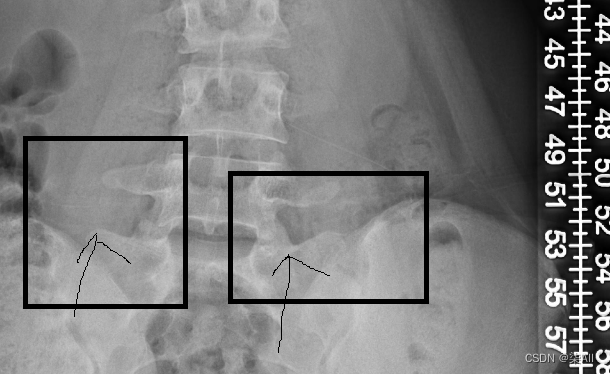

- (6)你看这种58这种点,咱们可以往外标一点,或者把60缩一些

(6)你看这种58这种点,咱们可以往外标一点,或者把60缩一些